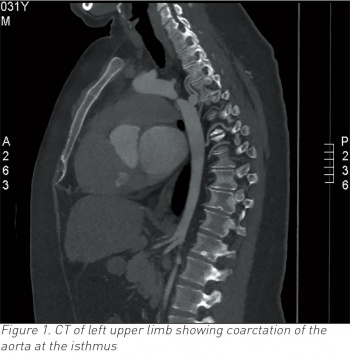

Two weeks following admission he complained of left arm pain and CT upper limb confirmed embolic occlusion of the left brachial artery and incidental severe coarctation of the proximal descending aorta after the origin of the left subclavian artery (see Figure 1).

CT left upper limb showed coarctation of the aorta at the isthmus (see Figure 1). The coarctation measures approximately 0.5-0.6cm, compared with 2.0cm in the distal arch and 2.7cm in the proximal descending and occlusion of the left brachial artery at the level of the distal third of the humerus.